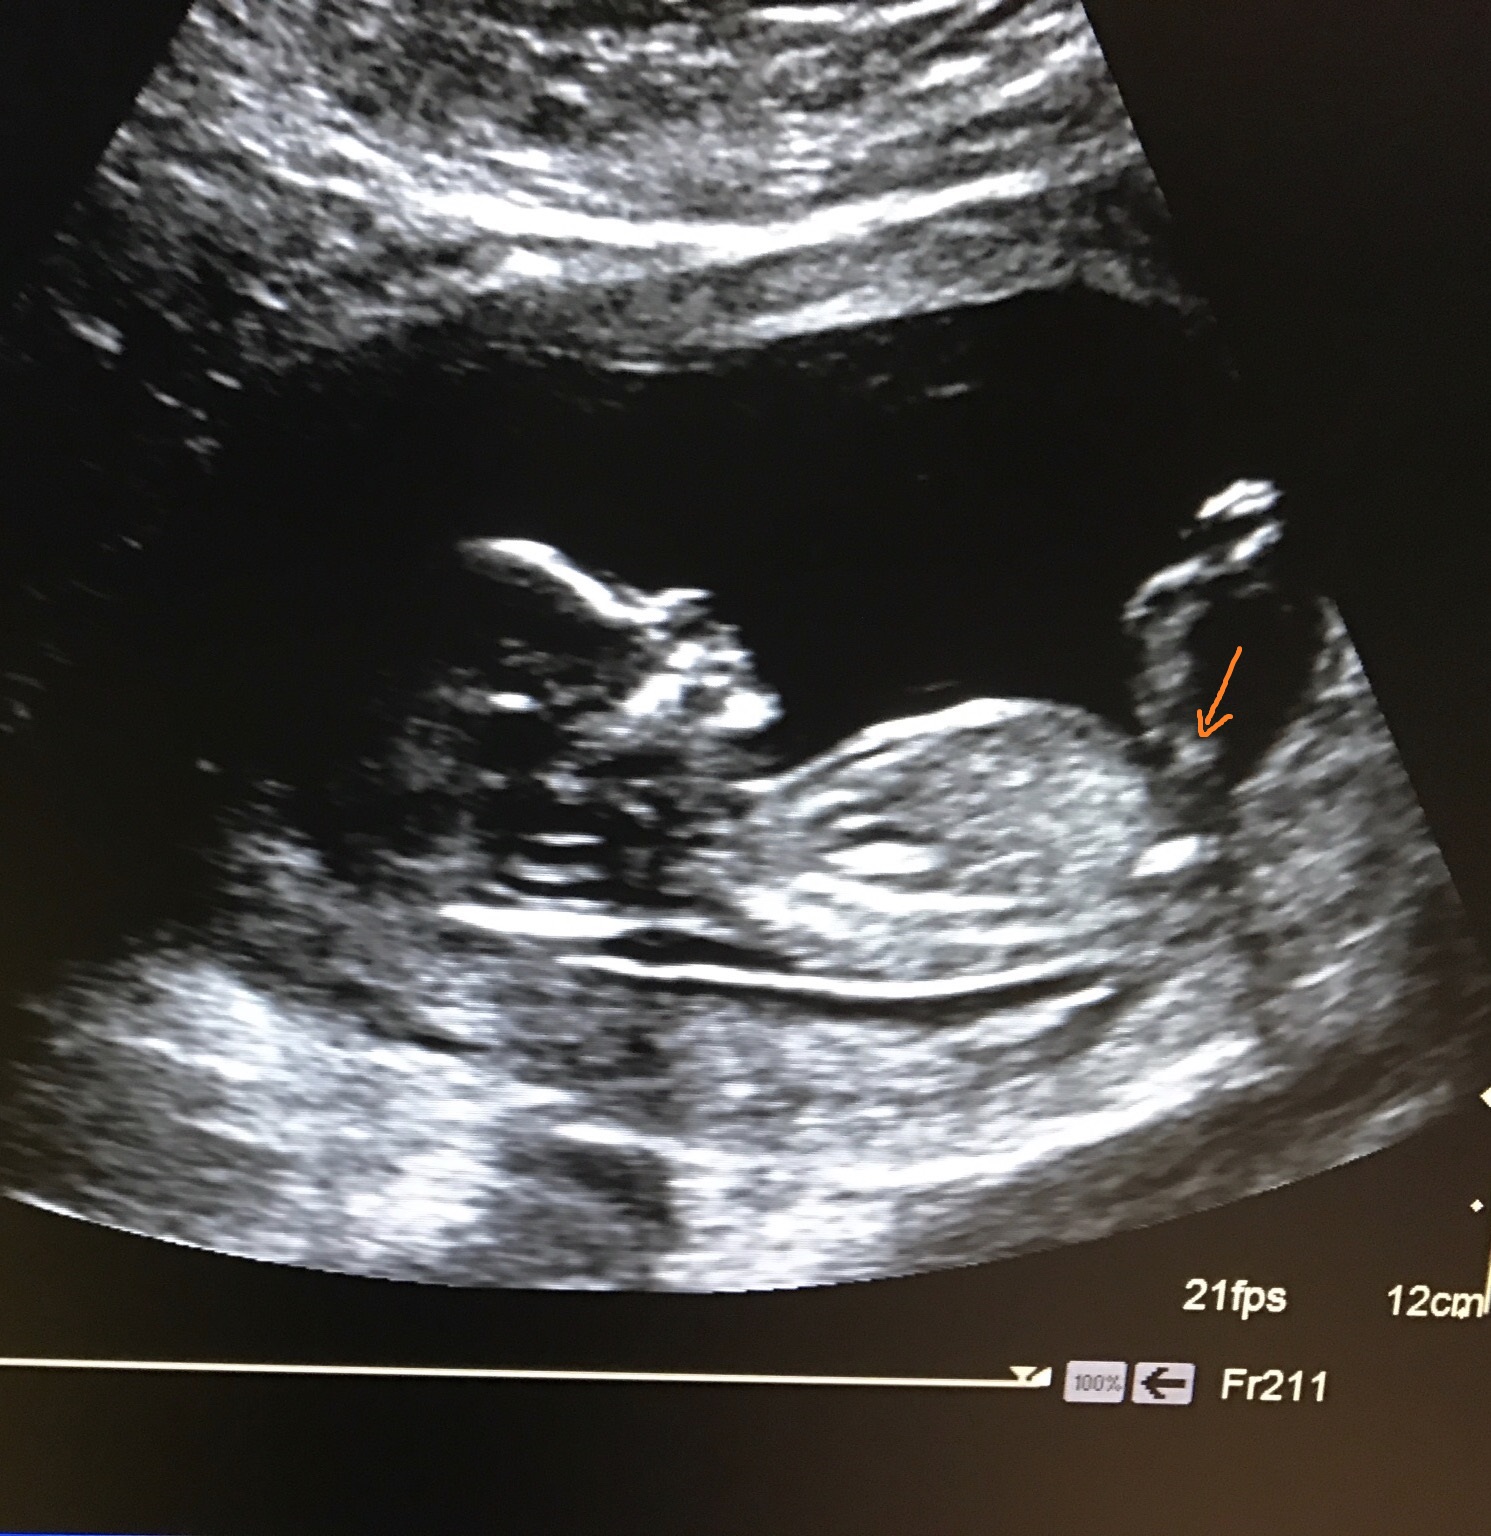

Here is an arrow pointing to the nub. As you can see, it's slightly pointing upwards, but it's not a straight forward boy nub, so this one could go either way IMO.

Attachment 34987